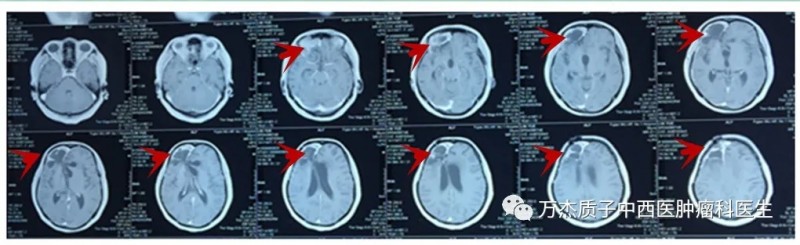

以下为患者治疗前后影像学检查资料:

2019-05-28手术前MR:肿瘤巨大

2019-07-20手术后MR: 术后需照射区域巨大

质子剂量分布图:肿瘤区域紧邻眼球及视神经,但质子射线完全避开眼球及视神经

2020-05-18治疗后8月复查MR:病情稳定

2020-11-19治疗后13月复查MR:病情稳定

此患者行质子放射治疗过程中耐受性良好,没有明显副作用出现。虽然肿瘤区域紧邻眼球、视神经,但质子射线避开了这些重要器官,患者视力完全没有受到影响,生活质量明显提高。从复查的头颅磁共振分析,患者肿瘤得到有效控制。建议患者3年内每3个月复查一次颅脑磁共振,并根据复查结果指导下一步治疗。